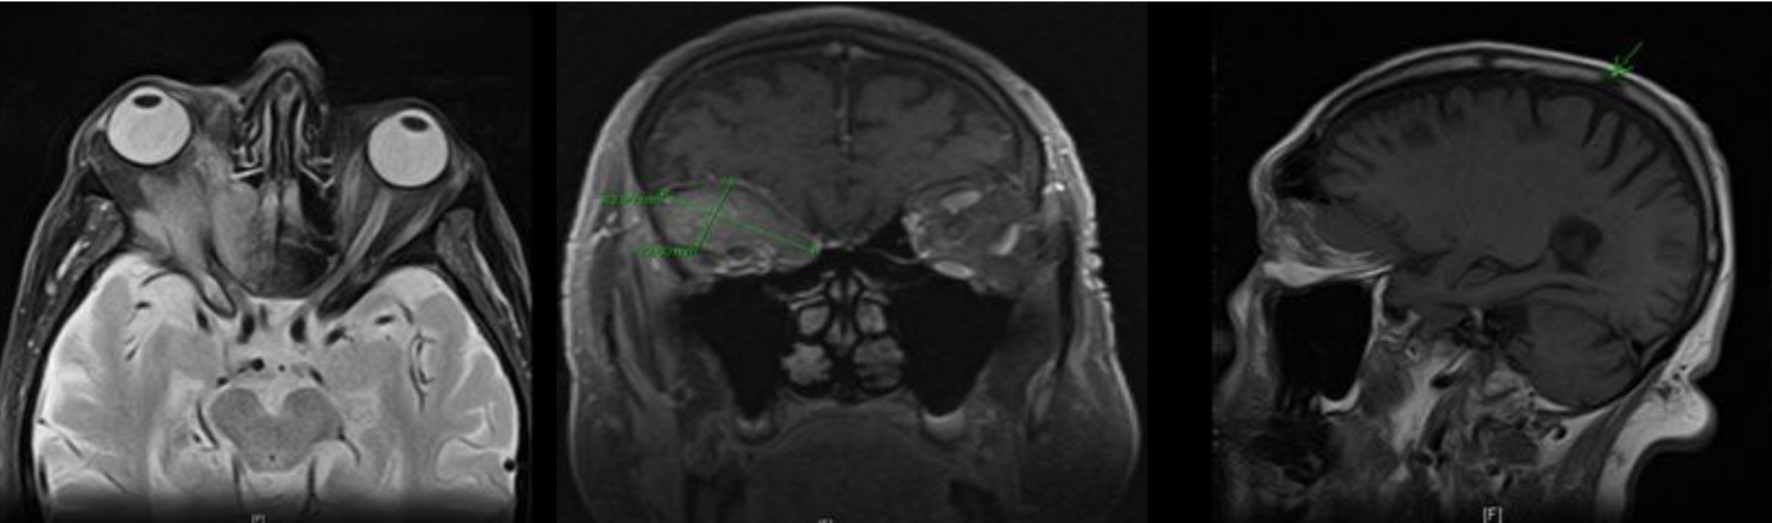

Magnetic resonance imaging (MRI) of the head revealed a hypointense, mildly enhancing, multi-compartmental soft tissue mass lesion in the superior right extraconal space measuring approximately 4.3 × 2.3 cm. This mass was seen extending and breaking through the orbital roof into the anterior cranial fossa superiorly, and medially extending into the lamina papyracea, posterior ethmoid sinus and the anterior lateral sphenoid sinus. Lateral extension into the posterior lateral orbital wall and sphenoid wing was noted. This mass was also seen wrapping and compressing the optic nerve sheath complex in the posterior intraconal space at the orbital apex. A 1.2 cm sclerotic lesion in the right parietal bone was also noted (Fig. 1). Patient underwent a right orbitotomy, and the biopsy of the orbital mass revealed a poorly differentiated adenocarcinoma.

![]() Click for large image | Figure 1. MRI of the head showing a right intra-orbital mass measuring 4.3 × 2.3 cm, extending into the anterior cranial fossa (superiorly); lamina papyracea, posterior ethmoid sinus and anterior lateral sphenoid sinus (medially); and posterior lateral orbital wall and sphenoid wing (laterally); sclerotic lesion in the right parietal bone also noted. |